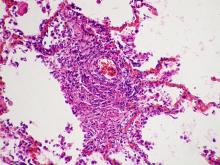

8. Antibiotics developed in 1960s show promise for TB therapy

September 28, 2016

First generation cephalosporins—antibiotics introduced as a treatment against bacterial infections in 1963—now show promise for tuberculosis (TB) therapy, according to new research published in Scientific Reports. Tuberculosis, caused by Mycobacterium tuberculosis, is the most deadly… read more

9. Researchers develop new weapon for hard-to-treat bacterial infections

September 27, 2016

Health workers may soon have a new weapon in the fight against abscesses—difficult-to-treat bacterial infections that lead to millions of emergency-room visits every year. Researchers at the University of British Columbia successfully prevented drug-resistant bacteria from forming abscesses… read more